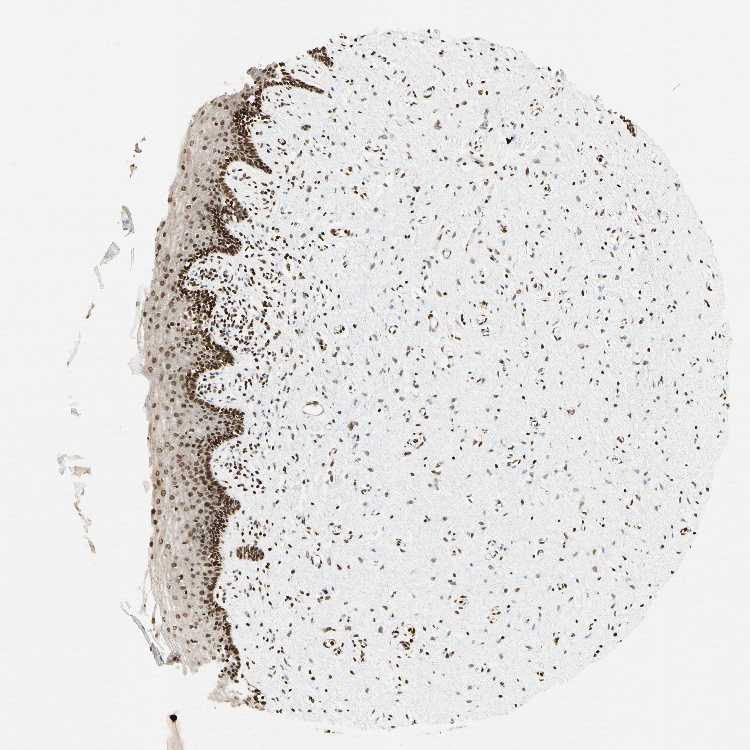

VAGINA - Antibody stainingi

Antibody staining in the annotated cell types in the current human tissue is reported as not detected, low, medium, or high, based on conventional immunohistochemistry profiling in selected tissues. This score is based on the combination of the staining intensity and fraction of stained cells.

Each image is clickable and will lead to virtual microscopy that enables deeper exploration of all samples and also displays staining intensity scores, fraction scores and subcellular localization as well as patient and tissue information for each sample.

Antibody HPA008834

Squamous epithelial cells High